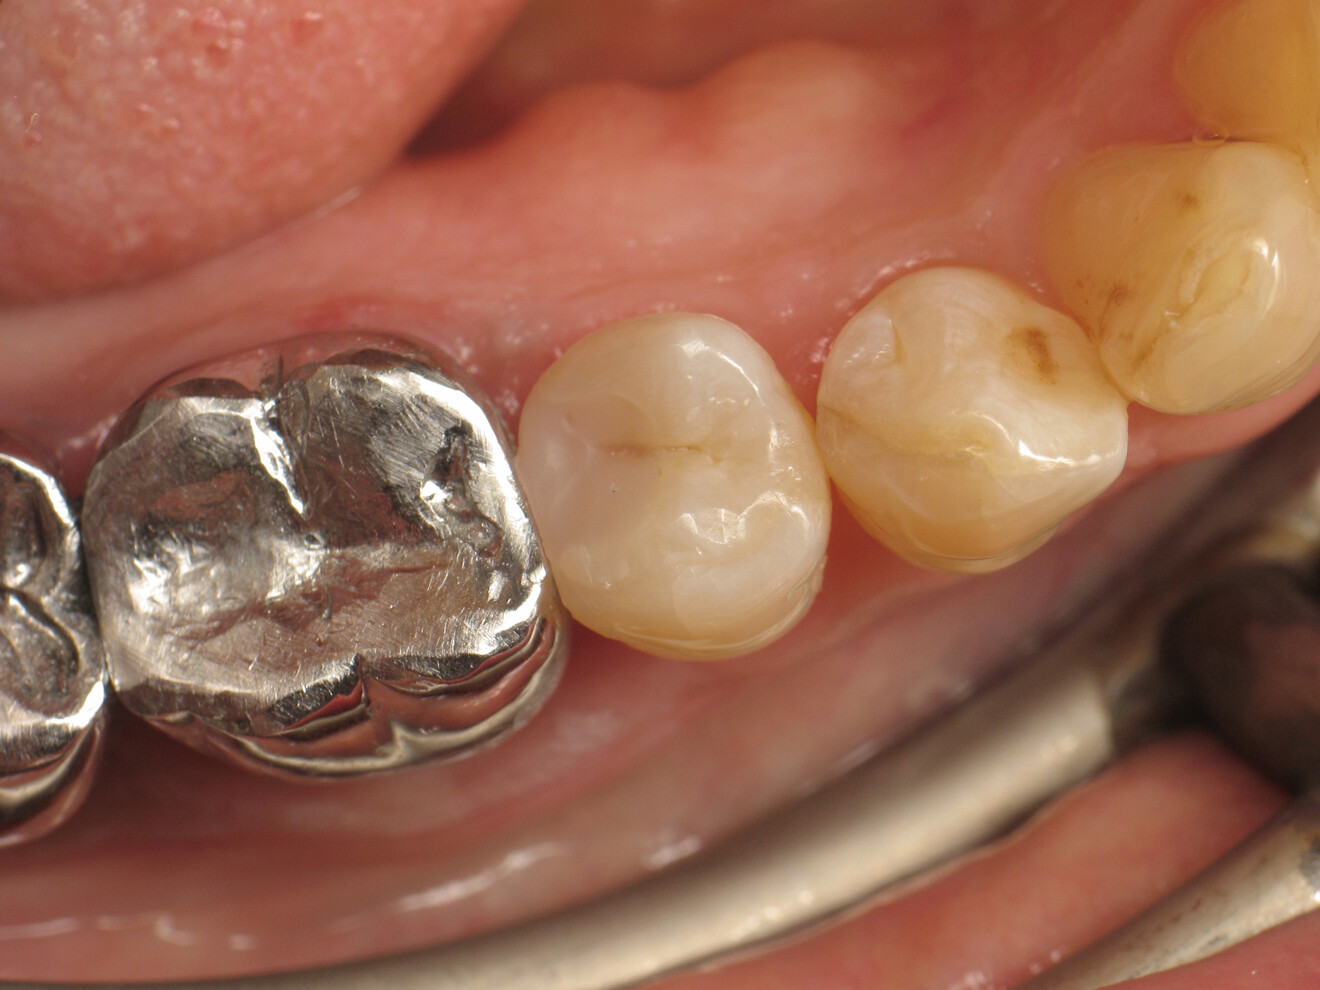

Fig. 22: Completed restoration after polishing.

The patient was very satisfied with the treatment results and impressed by the aesthetics of the restoration, which was barely distinguishable from the natural tooth. Furthermore, she was able to floss without any difficulty.